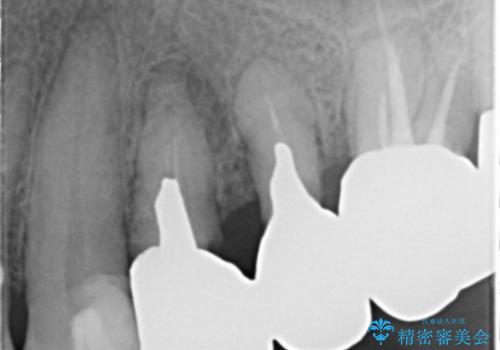

銀歯を除去したのち、虫歯を丁寧に除去し、歯を残せるのかどうかをしっかりと評価し、長期的な予後を見据えた虫歯治療を行っていきます。

銀歯の下で虫歯が再発していた歯は、無理に残しても割れてしまう可能性が非常に高いと考えたため、相談の上抜去を行いインプラント治療を行っていくこととしました。